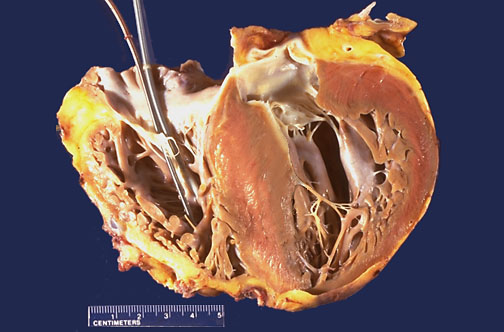

| There is marked left ventricular hypertrophy, with asymmetric bulging of a very large interventricular septum into the left ventricular chamber. This is hypertrophic cardiomyopathy. About half of these cases are familial, though a variety of different genes may be responsible for this disease. Both children and adults can be affected, and sudden death can occur. Seen here is the explanted heart. Pacemaker wires enter the right ventricle. The atria with venous connections, along with great vessels, remained behind to connect to the transplanted heart (provided by someone who cared enough to make transplantation possible). |